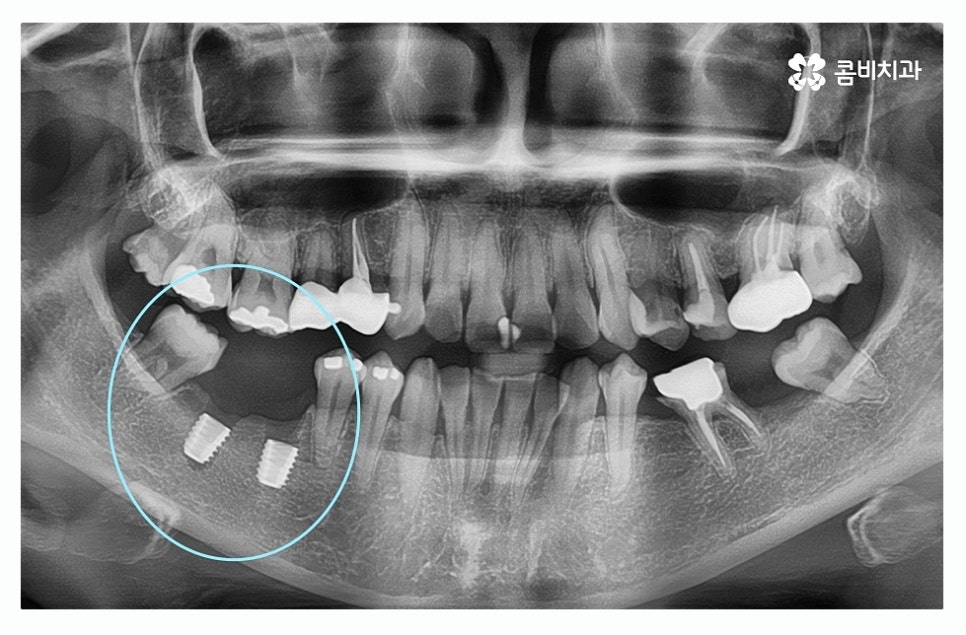

치주염이 심해져서 치아를 상실하게 되는 경우에는 치아를

한꺼번에 여러 개 잃게 되는 경우도 많기 때문에

임플란트를 하나만 식립하는 것이 아니라 여러 개 식립을

하는 경우가 있겠고 임플란트는 잇몸 뼈에 식립을

하기 때문에 치주질환이 심했던 경우 잇몸 뼈가 부족해서

뼈이식 임플란트나 상악동 거상술을 해야 하는 경우도 있어요.

오늘 보시는 환자분의 경우에는 치주질환이 심해져서

여러 치아를 발치하게 된 사례로 자연치아의

위 이미지에서 보시는 것처럼 치주염으로 인하여

잇몸뼈가 많이 내려간 경우 음식물이 잘 끼고 관리가 잘 안되면서

치아가 깊게 뿌리내리지 못해 흔들리게 되고

치아가 제대로 된 기능을 하지 못하여 발치까지 진행되는 경우가 있는데

위 환자분도 사랑니가 이런 경우에 해당되어 발치를 진행한 사례라고 할 수 있어요.